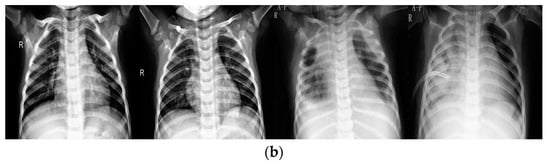

Figure 2 provides several examples between the original and enhanced images. Figure 2a represents examples from original data set, while Figure 2b represents examples from the enhanced data set. As shown, the upper images always contain gray and vague areas while lower images display almost white and black areas, showing that the enhancement technique plays a significant role in image contrast. In this study, the information implicit in original images, like bones, lung areas, and other tissues, is revealed by the DHE technique.

Figure 2.

Comparison of original and enhanced images. (a) Examples of original images; (b) examples of enhanced images.